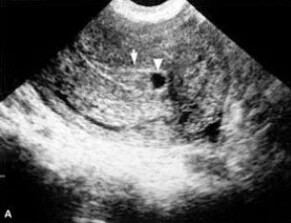

B超显像法

1)胎囊:超声诊断中最早出现的症状,妊娠4~5周时出现

2)胎心:妊娠第5周以后可以测得,早期妊娠的胎心约为150~170次/分

3)胎芽:妊娠第5周即可显示